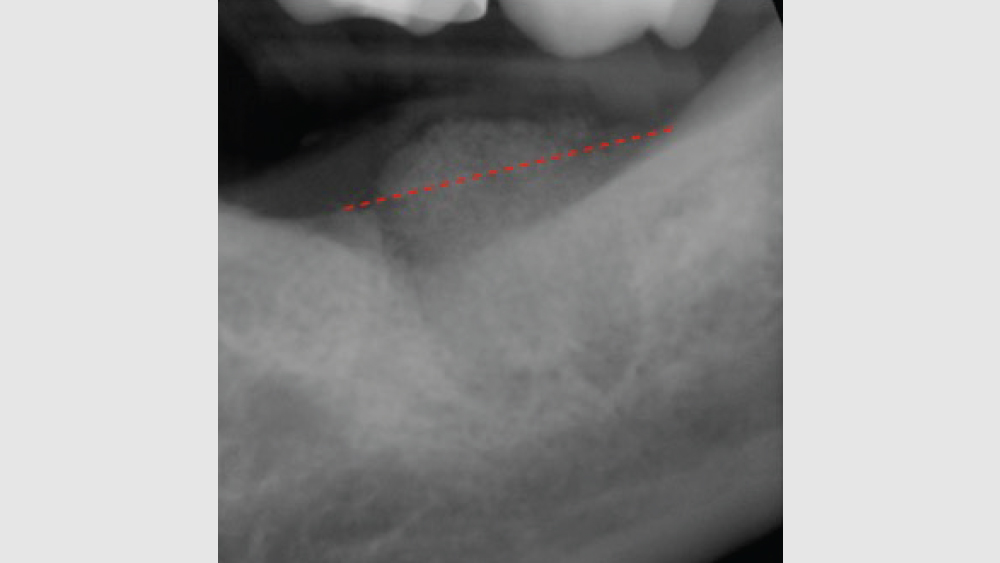

The most common complication from socket grafting techniques is inadequate bone graft fill (Figs. 9a, 9b). Care should be exercised to add bone in small increments, especially to ensure that bone is placed in the apical one-third of the socket. A bone packer should be used with good condensation to avoid air spaces. Additional complications include overfilling of the graft material (Fig. 10). Bone graft material should be placed at the level of the bony crest to allow space for the membrane. If excess bone graft material is condensed above the bone crest, delayed healing will occur.

Figure 9a

Figures 9a, 9b: Inadequate socket grafting with large voids in apical one-third (9a), inadequate bone fill with resultant air space (9b).